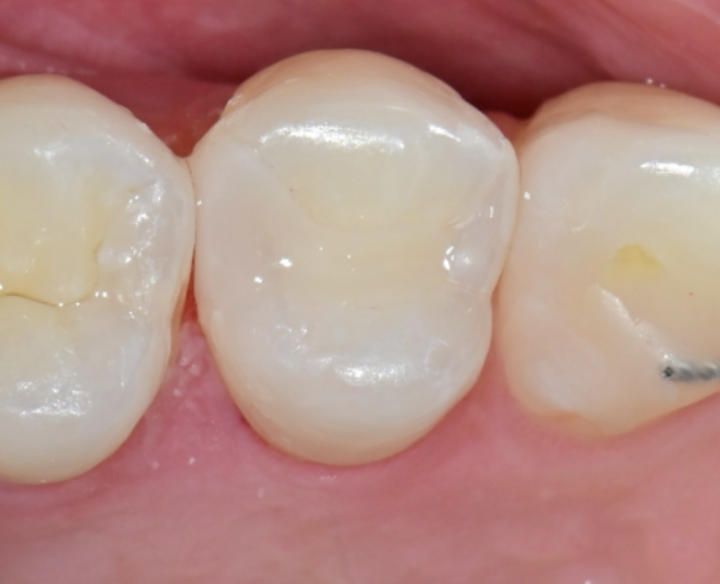

3️⃣ **초음파 기구(소닉라인)**로 정밀 연마→ 옆 치아 손상 없이 인레이 공간 정리

4️⃣ 디지털 스캔 → 당일 인레이 제작

→ 원내 보유 밀링 장비로 약 1시간 이내 제작

→ 임시치아 없이 당일 치료 완료

🦷 치료 후에는

자연치와 구분되지 않을 만큼 깔끔한 결과 + 편안한 저작감까지!